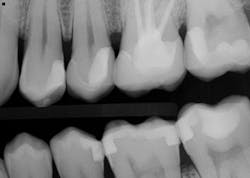

Figure 5: The radiographic results of the fillings, buildups, and bonded e.max restorations feature highly radiopaque bonding materials.